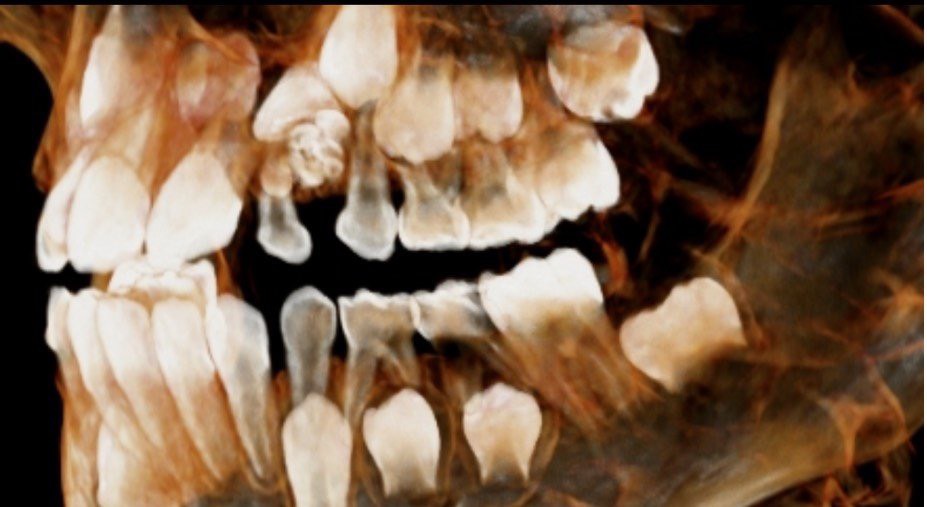

Trường hợp cháu N.T. T.D ( 9 tuổi, địa chỉ ở Minh Đức, Việt Yên) được bố mẹ đưa đến Bệnh viện Đa khoa tỉnh Bắc Giang khám do có răng thừa vùng hàm ếch. Sau khi được bác sĩ thăm khám và chụp X-quang xương hàm, phát hiện một khối u răng tương ứng với vùng răng số 22 và răng thừa vùng hàm ếch ngay sau răng số 11. Người bệnh được chẩn đoán: u răng vùng răng số 22 và được chỉ định phẫu thuật lấy u. Ca phẫu thuật kéo dài 60 phút, đã loại bỏ răng sữa số 2 bên trái, lấy răng thừa, loại bỏ khối u răng. Sau phẫu thuật bệnh nhân ổn định, vết mổ tốt, kiểm tra chụp X-Quang sau phẫu thuật không còn hình ảnh u răng.